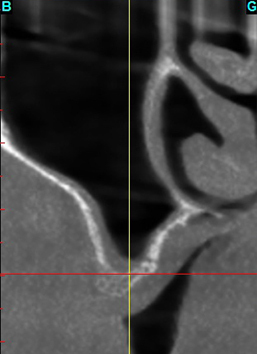

Nous retiendrons que le comblement sinusien est proposé quand il manque beaucoup de volume osseux et que le soulèvement sinusien est proposé lorsque le manque est faible.

Le comblement sinusien est une intervention plus longue, plus coûteuse et qui génère plus de suites opératoires que le soulèvement sinusien.